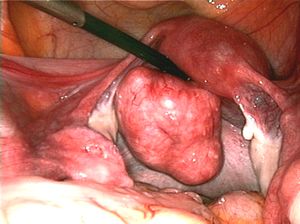

| Uterine fibroids as seen during laparoscopic surgery | |